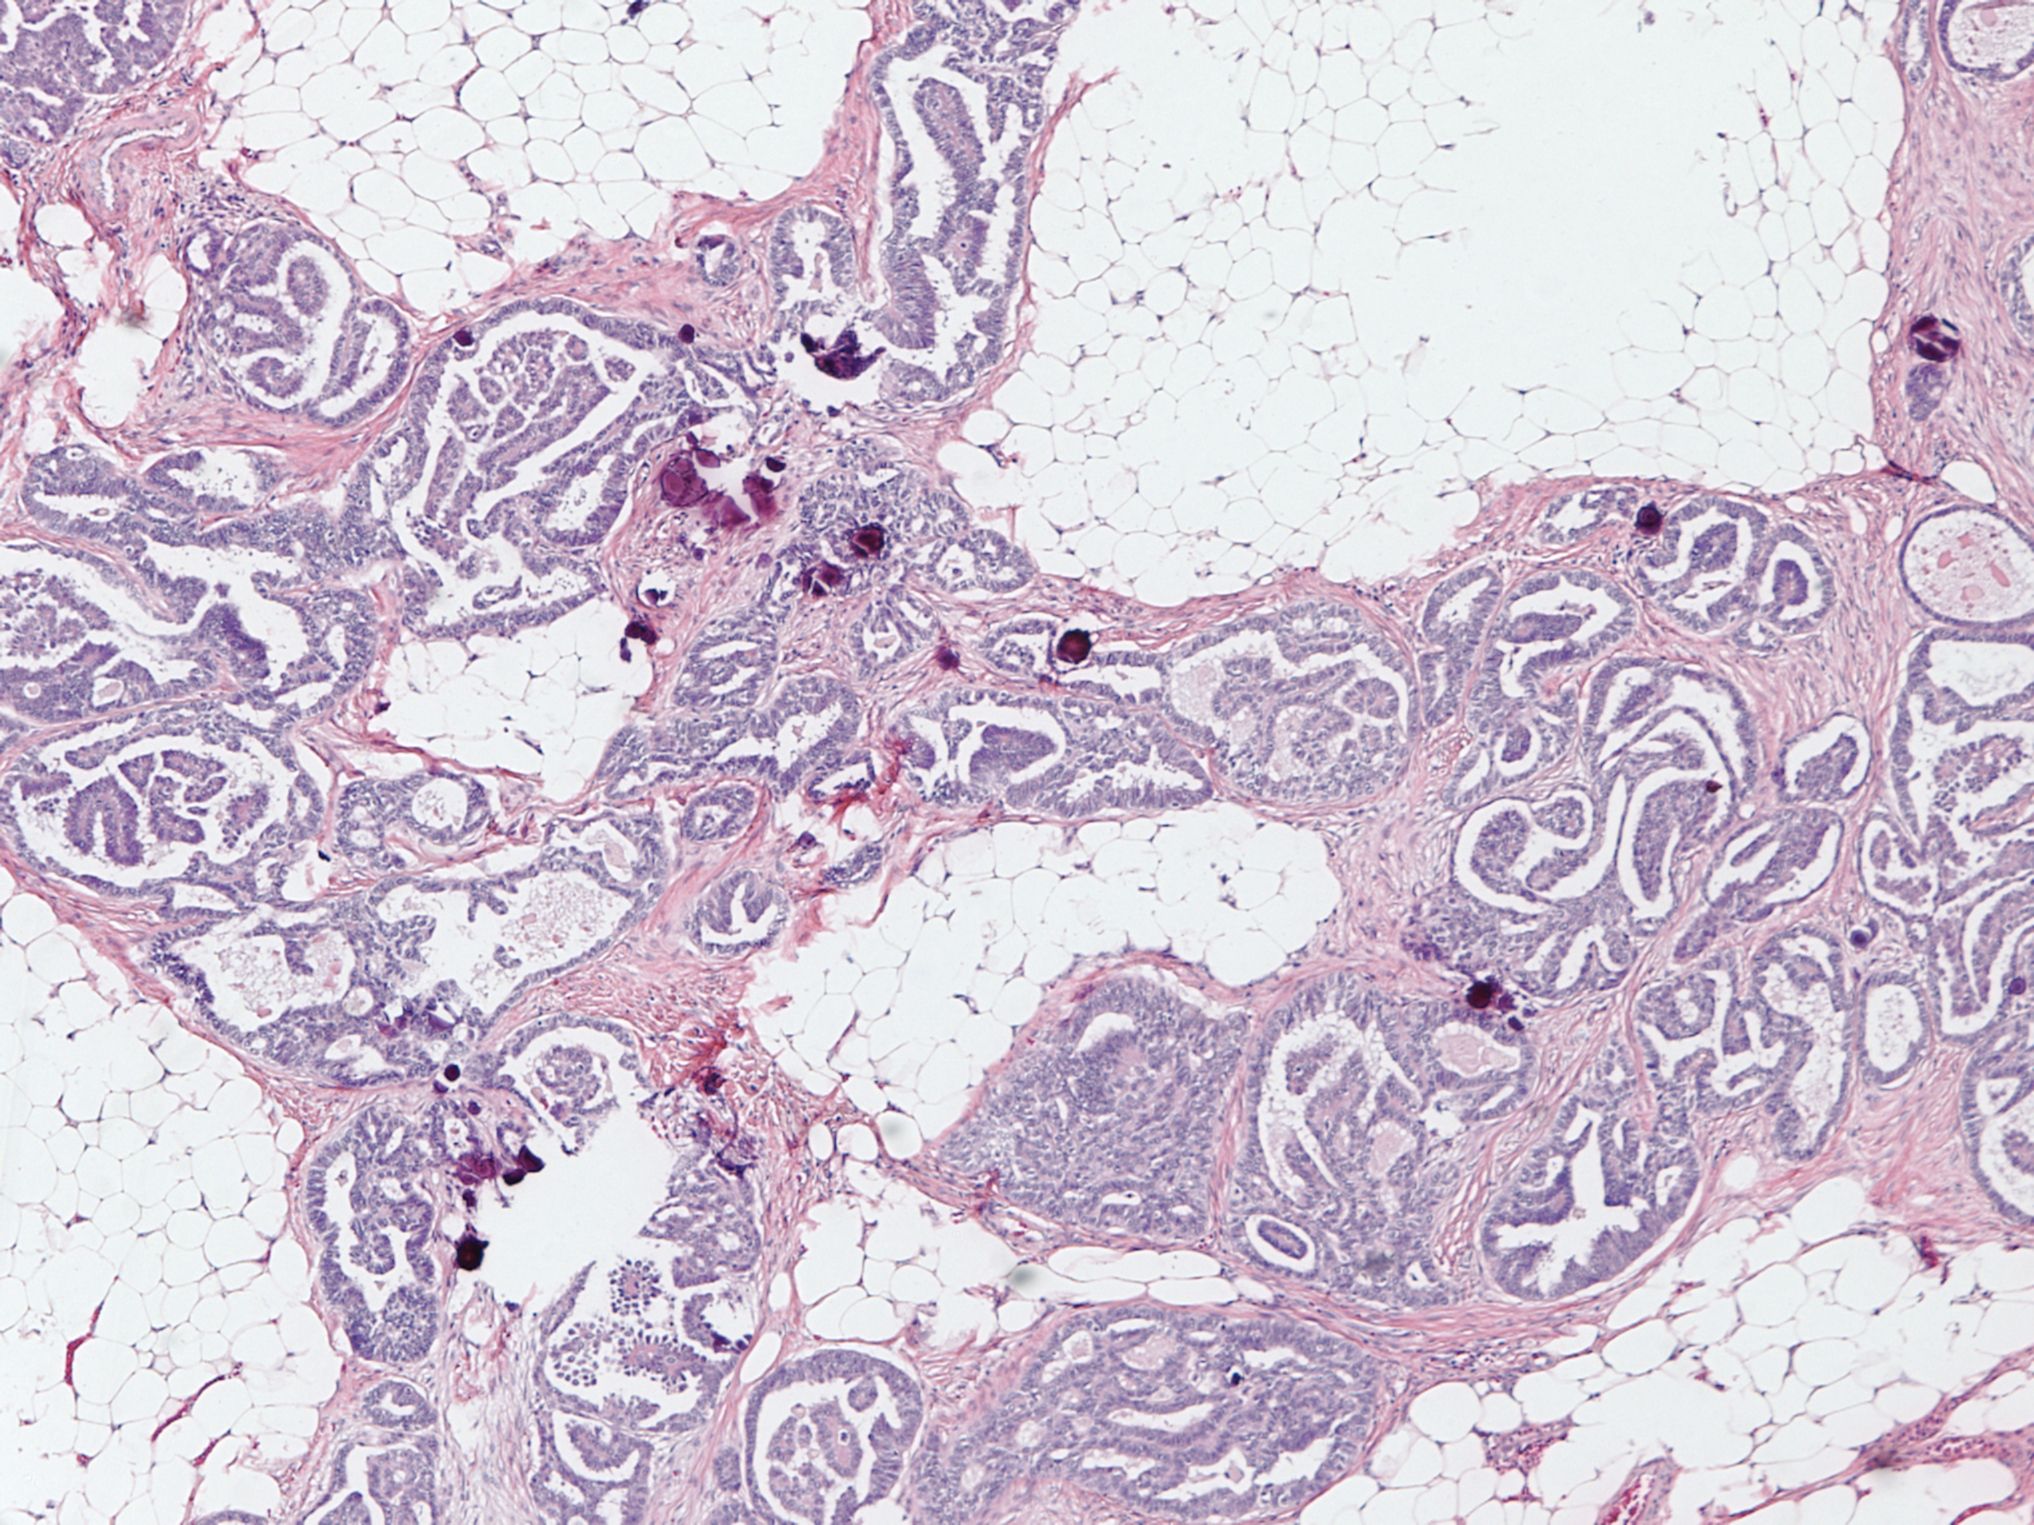

Microscopic (histologic) description

- Uniform / homogeneous population of small cells with scant cytoplasm

- Mild to moderate nuclear atypia at most (grade 1 or 2)

- No nuclear pleomorphism (< 3x variation in size) (Hum Pathol 2005;36:1049)

- May have a conspicuous nucleolus

- Low mitotic index: < 12 mitotic figures per 10 high power fields

- Little to no necrosis

- Psammoma bodies are frequent

- 2 patterns, noninvasive and invasive:

- Noninvasive: nonhierarchical architecture with micropapillary or cribriform patterns with significant expansile growth

- Invasive (> 5 mm): micropapillary or complex papillae, compact cell nests, inverted macropapillae (with broad fibrovascular cores), cribriform, glandular or cystic, solid sheets with slit-like spaces and single cells

- Multiple different invasive patterns can exist within one tumor

Microscopic (histologic) images